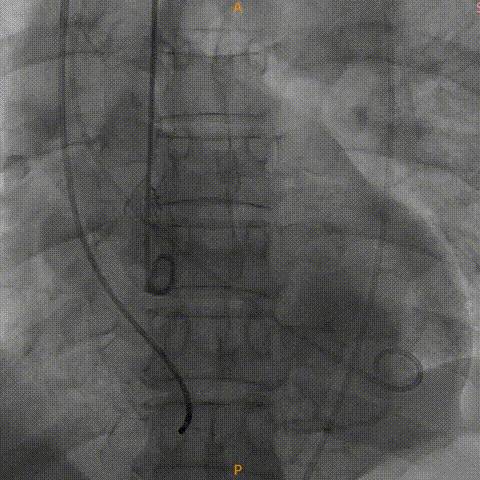

造影显示有瓣周漏

植入瓣中瓣

瓣中瓣形态良好,无反流